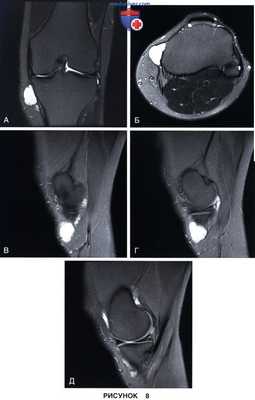

• Перименисковая киста (рис. 8)

РИСУНОК 8. Локализация заднемедиального (А) и заднелатерального (Б) портов с помощью спинальной иглы и соответствующая артроскопическая картина заднемедиального отдела коленного сустава при синовиальном хондроматозе с фиксированными внутрисуставными хондромными телами (В) и в норме (Г).